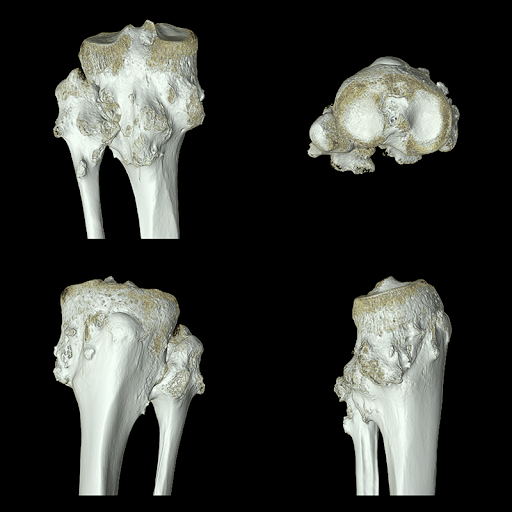

Визуализация опорно-двигательного аппарата